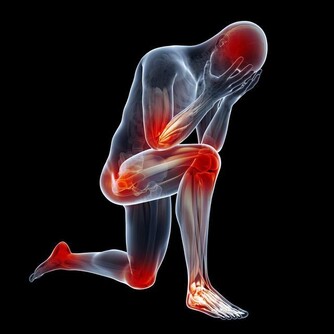

多發性骨髓瘤這種疾病多發於老年人,並且年齡越大發病率越高,是成正比的,這種疾病最初的表現症狀也是腰痛,但是除了腰痛之外,這個疾病還會侵犯身體其他的骨頭,也就會導致身體其他部位的疼痛,多發性骨髓瘤會侵犯人的運動系統,最嚴重的後果是導致骨折,老年人的骨折往往都是致命的,因為老年人骨折後的臥床會帶來很多的並發症。

多發性骨髓瘤這種疾病多侵犯人的骨頭、骨髓,所以常常腰痛伴有周身疼痛,並且多發性骨髓瘤這種疾病也是一種惡性腫瘤,如果家裡的老人長時間的腰痛就要帶著去醫院檢查一下,排查一下多發性骨髓瘤。